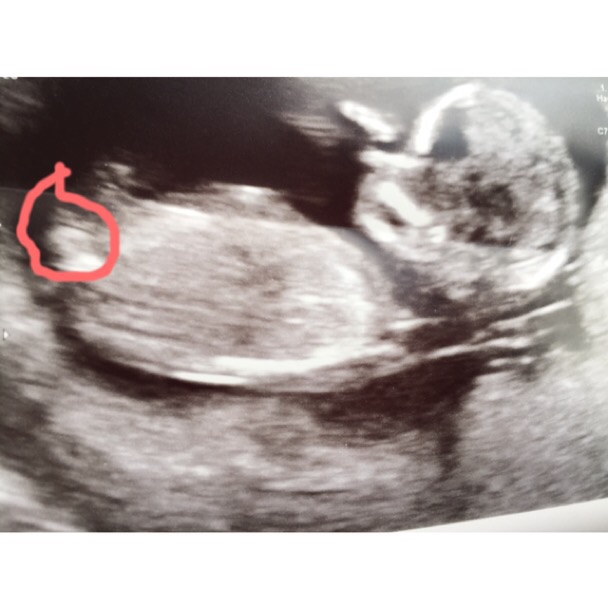

Can you take the drawing off plz :)

Thinking boy

Looking like a boy.